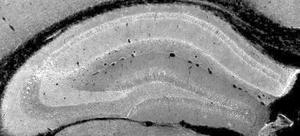

Descubren las neuronas que reescriben los recuerdos más traumáticos